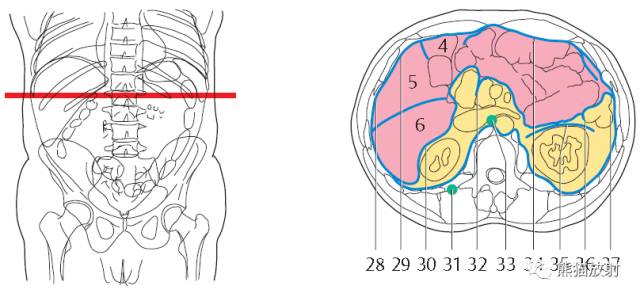

第二层

腹腔(粉色);腹膜后(黄色)

1、肝右叶;2、下腔静脉;3、肝尾状叶;4、肝门静脉;5、肝左叶;6、胃左动脉;7、腹直肌;8、膈肌;9、胃;10、结肠左曲;11、腹外斜肌;12、胸导管;13、奇静脉;14、腹主动脉;15;胸椎;16、最长肌;17、椎管和脊髓;18、棘肌;19、髂肋肌(胸段);20、脾脏;21、左肺;22、背阔肌;23、肋膈隐窝;24、右膈下隐窝;25、肝裸区;26、膈上淋巴结;27、肋间淋巴结;28、后纵隔;29、膈下淋巴结;30、左侧结肠旁沟。